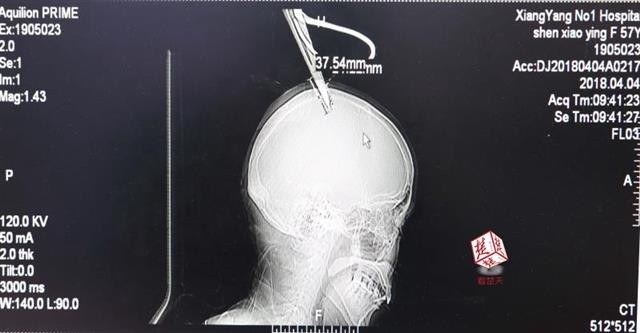

▲女子頭上插了剪刀。(圖/翻攝自陸網)

襄陽市樊城區太平店鎮一名婦女在田裡工作時,不慎將綁在竹竿上的剪刀用掉,直接插進頭驢上,但她卻非常冷靜,甚至沒有坐救護車,和家人坐了1個小時的公車去市區的醫院,所幸治療後無大礙。

綜合陸媒報導,57歲的沈女在摘香椿嫩芽時,原本綁在竹竿上的剪刀,卻因為竹子腐爛斷裂,不慎插入她的頭中,但她回憶時說,感覺沒什麼大礙,只覺得頭有點遲鈍,因此捨棄了叫救護車,只坐了公車慢慢的坐去醫院。

醫生檢查發現,剪刀刀尖斜嵌在沈女的顱骨裡,離腦髓只有2、3公厘,幸好是斜著插進去,如果垂直刺入,很有可能造成癱瘓,經過手術後順利將剪刀取出,目前生命已無危險,但仍在加護病房進一步觀察。